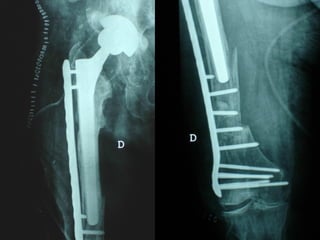

Dal Gennaio 2000 al Dicembre 2005 27 placche LISS di femore

INDICAZIONI COMUNI Fratture sovracondiloidee Fratture intercondiliodee Fratture diafisarie distali PARTICOLARI Fratture con grave osteoporosi Fratture periprotesiche

VANTAGGI CHIRURGIA MININVASIVA Mini Open Inserimento della placca sottocutaneo per scivolamento Viti percutanee Preservazione dei tessuti molli Ridotto danno vascolare Rapida ripresa funzionale

F, 68 y

LISS  NCB

NCB